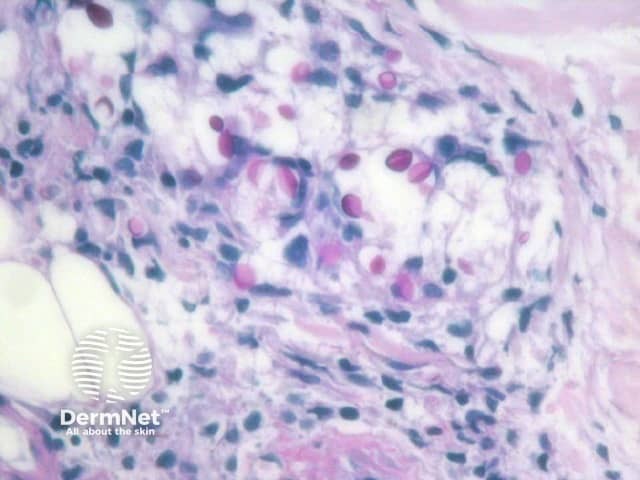

The yeast forms of cryptococcosis are usually surrounded by massive gelatinous oedema (figure 1, arrow). The surrounding inflammatory reaction depends on the stage of the clinical lesion and on the immune status of the patient. Immunocompetent patients may elicit a brisk granulomatous response in which the organisms may be difficult to see without special stains, while immunocompromised patients show minimal inflammation and oedema around the numerous yeast forms as seen in the case illustrated here (figure 2). The yeast forms of cryptococcosis are usually widely separated by their thick mucoid capsules. PAS stain decorates the yeasts (figure 3) and mucicarmine stain decorates the highly characteristic gelatinous capsule a bright pink (figure 4).

Figure 4

The cryptococcus capsule stains intensely with the mucicarmine stain (figure 4). Grocott, mucicarmine, methenamine silver, toluidine blue, or methylene blue are sometimes required help illustrate the characteristic budding yeasts. This is especially helpful in immunocompetent hosts with a brisk inflammatory response.